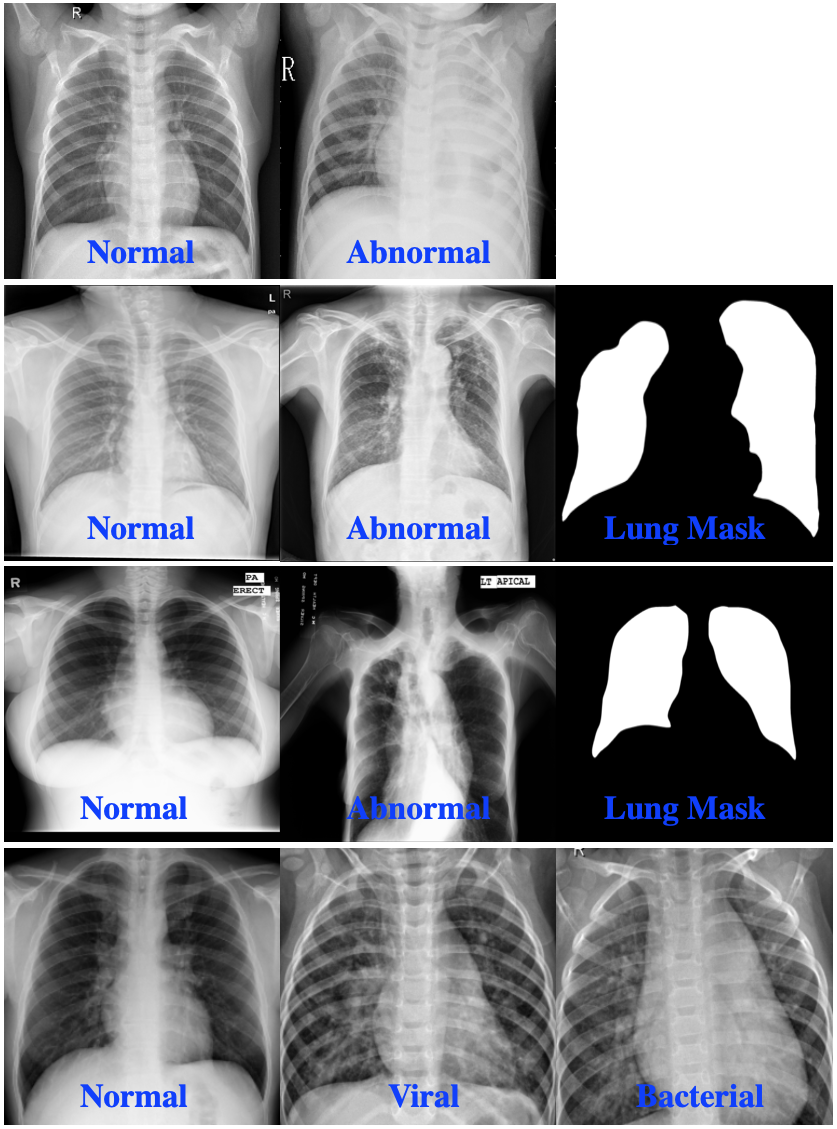

| Modality | Dataset | Total Images | GT Labels | Resolution |

| RSNA | 26,684 | Normal | 1024 x 1024 | |

| Abnormal | ||||

| Shenzhen | 662 | Normal (336) | 3000 x 3000 | |

| Abnormal (326) | ||||

| Lung mask (566) | ||||

| CXR | Montgomery | 138 | Normal (80) | 4020x 4892 |

| Abnormal (58) | ||||

| Lung mask (138) | ||||

| Pediatric | Train: 5,232 | Bacterial (2,538) | – | |

| Pneumonia | Viral (1,345 ) | |||

| Normal (1,349) | ||||

| Test: 624 | Bacterial (242) | |||

| Viral (148) | ||||

| Normal (234) | ||||

| Doppler | 2444 | Doppler Flow (2444) | – | |

| Tasks | Image Quality (814) | |||

| Envelope mask (2444) | ||||

| Doppler | ||||

| Echo | ||||

| Doppler | MV Flow (855) | |||

| Flows | MA Flow(490) | |||

| TR Flow (1099) |

3.1 Medical Image Datasets

Two medical imaging modalities are used to evaluate the proposed approach described in Section 3.2. These modalities are chest X-ray (CXR) and Doppler echocardiography (Doppler echo). Table 1 provides a summary of the CXR and Doppler echo datasets used in this work.